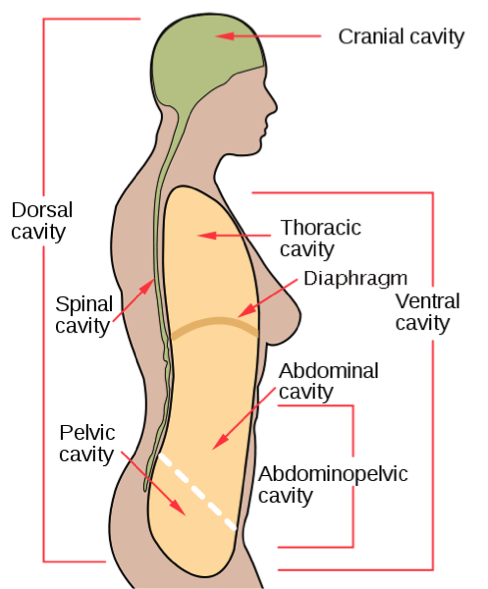

Cranial cavity

the hollow space in the brain that houses and protects the brain

Spinal cavity

the hollow space within the spine that houses and protects the spinal cord

Ventral body cavity

the front space from the neck to the pelvis divided into two parts: thoractic and abdominopelvic cavity

Pelvic cavity

bowl shaped space below the abdomen enclosed by the pelvic bones

Diaphragm

thin dome-shaped, musuclar partian seperating the throractic and abdominal cavity

Abdominal cavity

large space between diaphragm and pelvis

Thoracic cavity

refers to the chest cavity